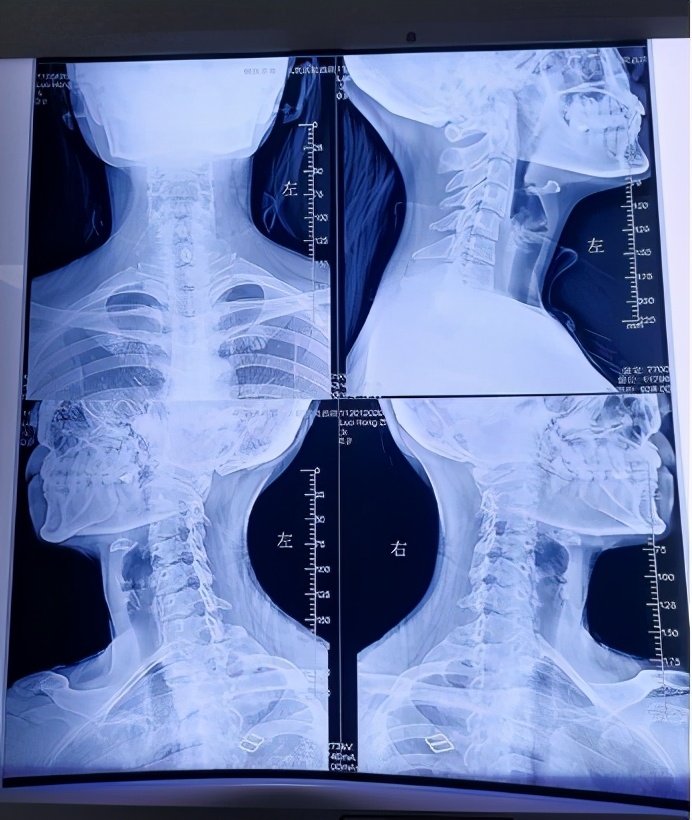

颈椎退变、反弓,右侧C3/4椎间孔狭窄

枕寰间隙缩小,齿状突关节左偏

胸腰段脊柱向左侧弯

骨盆右倾旋转